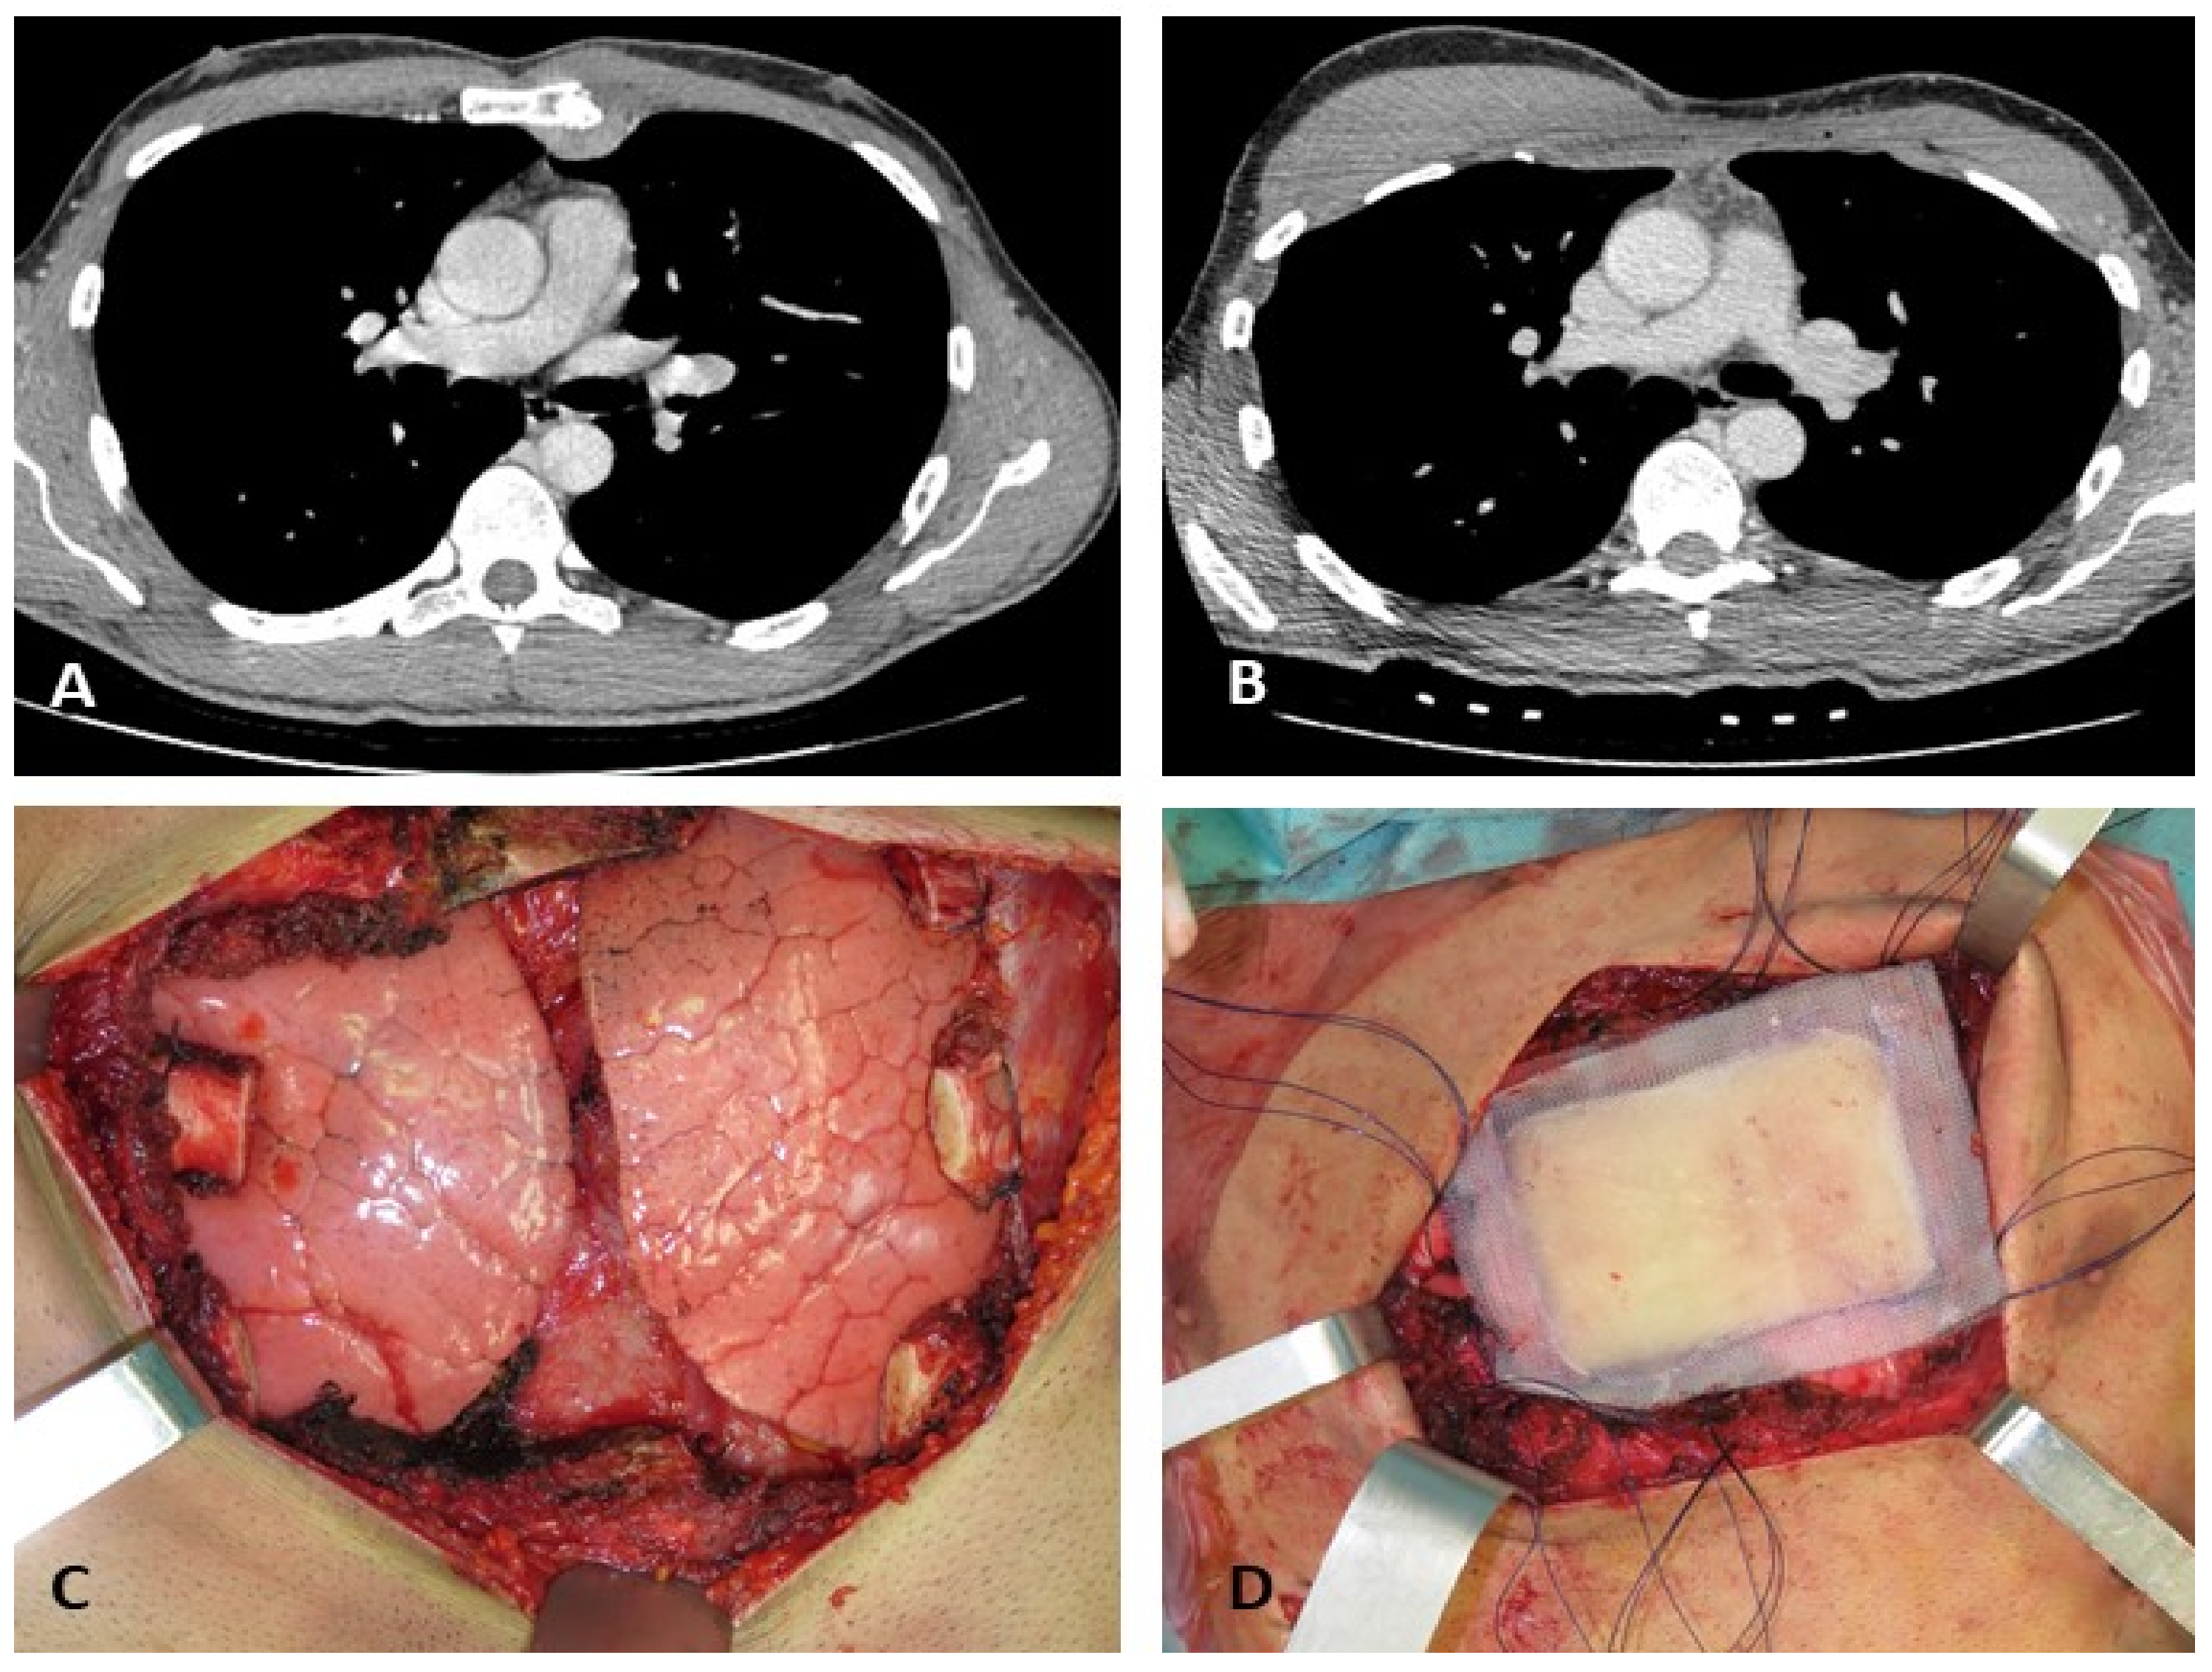

Grade 1 and 2 Chondrosarcomas of the Chest Wall: CT Imaging Features and Review of the Literature

3. Results

4. Discussion